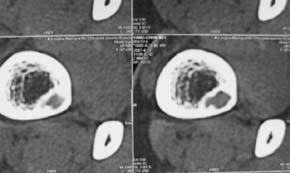

男,中学生打篮球时右踝扭伤,拍片时发右胫骨下端楕圆形透亮影,是不是动脉瘤样骨囊肿,请讨论

骨皮质内破坏区,其下部可能为“巢中有蛋“征,首先考虑骨样骨瘤,本病须与骨皮质脓肿,硬化性骨髓炎、骨梅毒等疾病鉴别。请结合临床进一步鉴别。

胫骨后外侧见囊样低密度边缘硬化,其内见小点状高密度影,首先考虑骨样骨瘤

应该是比较典型的非骨化性纤维瘤:病灶偏于骨干的一侧,紧靠皮质下,呈类圆形,靠近髓腔侧有硬化边,病灶长轴平行于骨干,周围无骨膜反应和软组织肿块。与骨样骨瘤鉴别:后者具有明显或剧烈疼痛,“瘤巢”为其特征,在瘤巢周围有显著的反应性骨质增生。